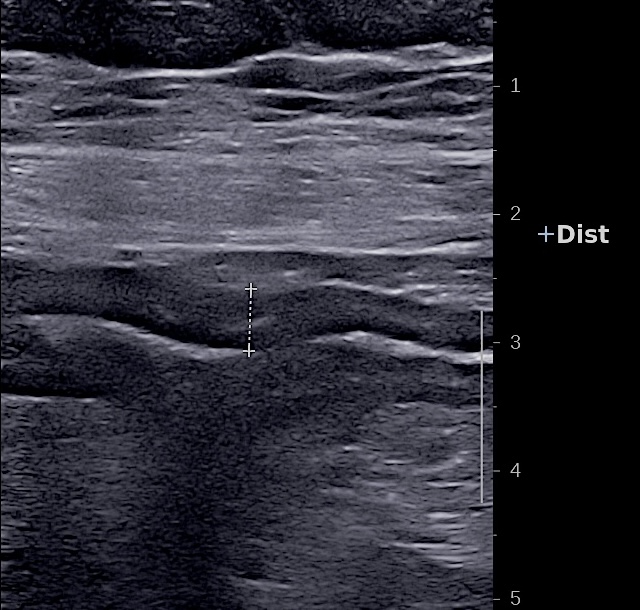

L'épaississement se mesure entre la muqueuse (hypoéchogène) et la musculeuse (hypoéchogène),

Ci dessous même portion avec et sans compression douce.

Il faut faire la moyenne de plusieurs mesures (≥3) en coupe longitudinale et transversale